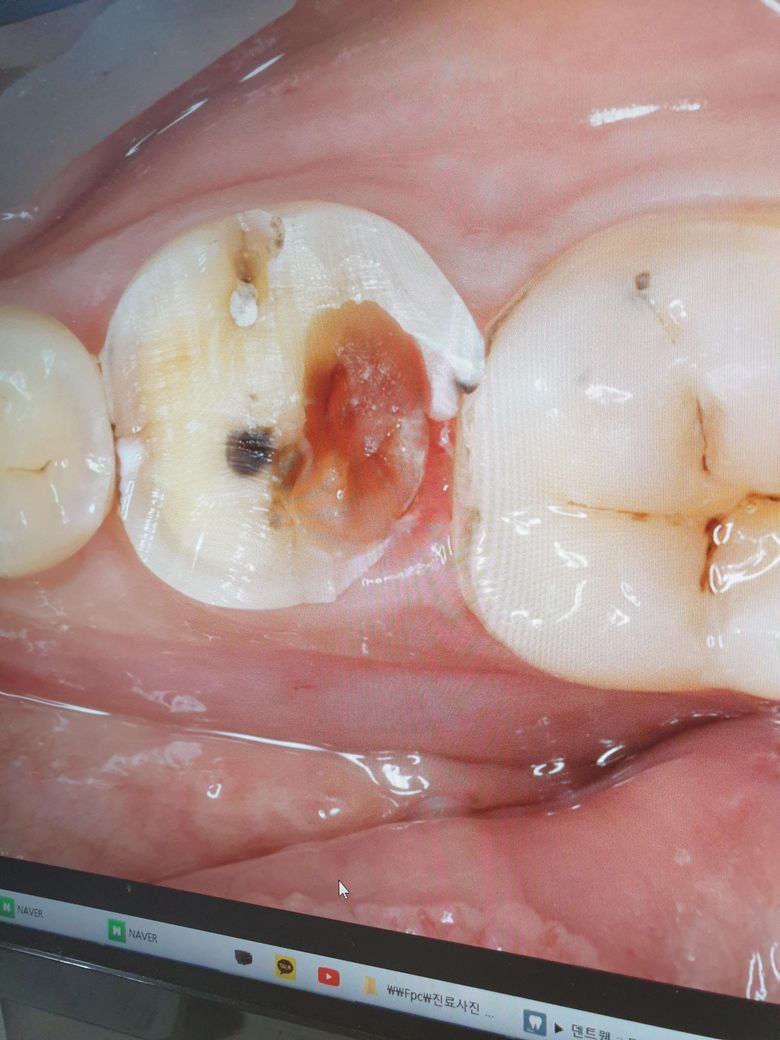

치아 과잉진료를 당해 멀쩡한 어금니를 뽑았습니다..

차아 과잉진료를 당해 멀쩡한 어금니를 그냥 뽑은것같아서 너무 속상합니다..

충분히 살려서 신경치료 해줬을수도 있었을텐데...

이정도면 신경치료가 왜 안되는걸까요...

현재 사진만으로는 정확한 판단이 어렵습니다. 다만 충치 범위가 치아 뿌리까지 내려갔다면 더 이상 신경치료는 불가능할 수 있습니다. 현재 사진이 아닌 x-ray 등으로 촬영했을 때 root까지 충치가 있다면 치아는 더 이상 살릴 가능성은 없습니다.

해당 치아를 살릴 수 있는 치과는 거의 없을 것 같습니다. 과잉진료라고 하기엔 어려움이 있습니다.

치과의사마다 생각은 다를 수 있습니다 흔히말해 저렇게 옆구리가 터진 치아는 신경치료를 해도 살리기 어려운 경우, 신경치료를 해도 금방망가지는 경우가 많습니다